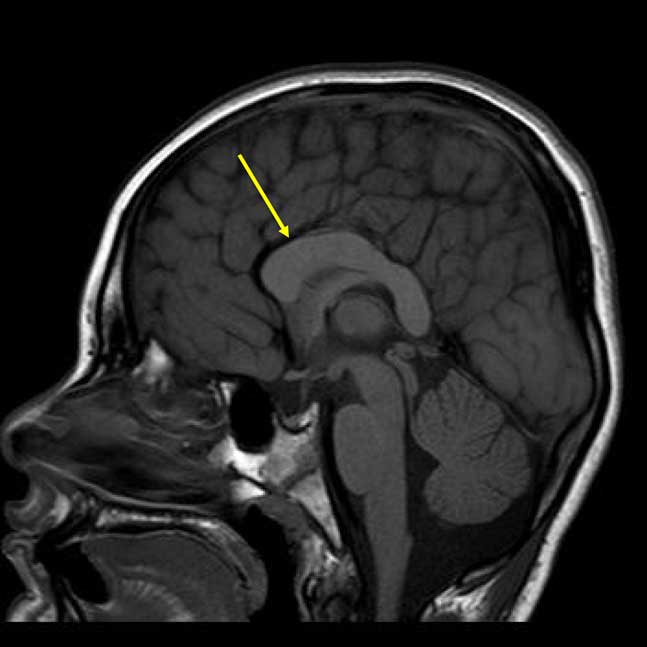

Neuroimaging often demonstrates non-specific abnormalities including dysplasia of the corpus callosum, bulging of the caudate nuclei, enlarged asymmetric ventricles, and cerebral atrophy, but no pathognomonic finding has been described (Andrieux et al., Reference Andrieux, Lepretre, Cuisset, Goldenberg, Delobel, Manouvrier-Hanu and Holder-Espinasse2008; de Pontual et al., Reference de Pontual, Mathieu, Golzio, Rio, Malan, Boddaert and Amiel2009; Giurgea et al., Reference Giurgea, Missirian, Cacciagli, Whalen, Fredriksen, Gaillon and Moncla2008; Peippo et al., Reference Peippo, Simola, Valanne, Larsen, Kahkonen, Auranen and Ignatius2006; Stavropoulous, MacGregor, & Yoon, Reference Stavropoulous, MacGregor and Yoon2010; Zweier et al., Reference Zweier, Sticht, Bijlsma, Clayton-Smith, Boonen, Fryer and Rauch2008). Neurodevelopmentally, most cases of PTHS are characterized by severe intellectual disability (ID), global developmental delay, and comorbid autism spectrum disorder (ASD; Cody et al., Reference Cody, Sebold, Heard, Carter, Soileau, Hasi-Zogaj and Hale2015; Sweatt, Reference Sweatt2013; Van Balkom, Vuijk, Franssens, Hoek, & Hennekam, Reference Van Balkom, Vuijk, Franssens, Hoek and Hennekam2012). Speech is often absent, and motor delays (independent ambulation after 5 years of age or not at all), ataxia, and motor incoordination occur in the majority of cases.

The patient’s most recent magnetic resonance imaging (MRI) at age 9 years is shown in Figure 2. Results revealed a dysmorphic corpus callosum that was slightly shorter in anteroposterior dimension and thicker than normal, consistent with corpus callosal abnormalities described in the PTHS literature. The retrocerebellar cerebrospinal fluid spaces were also noted to be prominent, but insignificant, and no additional parenchymal abnormalities were found. Facial features consistent with PTHS were observed, including midface flattening, mild hypotelorism, bulbous nasal tip, and Cupid’s bow lip. Appearance was also significant for slightly prominent finger pads and toe pads. No significant findings were found on recent neurological review of systems including cranial nerve, sensory, cerebellar, reflexes, and gait examination. Examination of motor systems revealed hypotonia, but normal strength. Finally, a recent mental status examination revealed adequate eye contact, normal orientation, good cooperation, and ability to speak in full sentences despite poor articulation and immature content/syntax.

Fig. 2 Sagittal T1-weighted magnetic resonance imaging demonstrating the dysplastic corpus callosum (arrow).